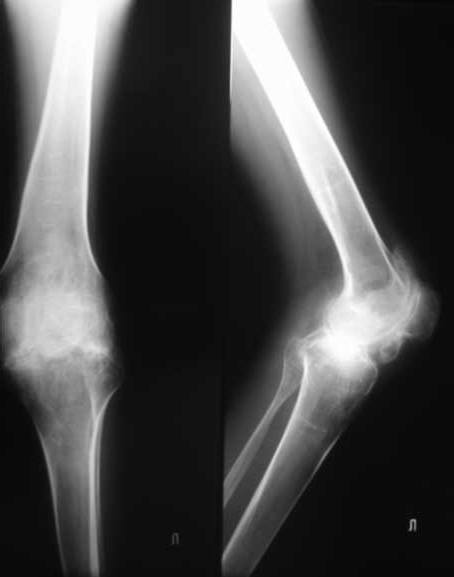

Уважаемые коллеги. пациент, страдает ревматоидным артритом с детства, ранее докладывался...

костный анкилоз т/б суставов. 4 месяца назад THR левого т/б сустава, движения в т/б суставе приличные - с/р 90/5/0, движения в коленном суставе ухудшились - с/р 120/45/0. В настоящее время конечность неопорна из-за сгибательной кнтрактуры в к/с Вопросы о дальнейшей тактике лечения (пациенту 28 лет):1. рассматриваются варианты остеотомий (бедра, б/б кости), насколько это целесообразно, учитывая необходимость артротомии (остеофиты), каков может быть ожидаемый результат? варианты остеотомий (бедро или голень)?2. эндопротезирование к/с: мягкотканный дисбаланс- достаточно будет релиза капсулы и связок или мышцы тоже (учитывая разгибание в т/б после эндопротезирования и натяжение мышц на уровне колена после этого) Чего опасаться и к чему быть готовым?3. другие варианты? ссылки на литературу?собств наблюдения?С уважением Максим Агалаков

Нет снимков коленного сустава. Видимо у А.Н. руки не дошли.